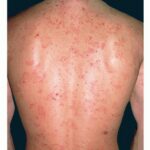

Although the relatively low titer of IgA antibodies against the basement membrane present in the sera of patients with both linear IgA dermatosis and CBDC has complicated the search for specific antigenic targets for the IgA, several investigators have made significant observations regarding the antigenic targets in these diseases. Zone et al.24 studied sera from patients who had circulating IgA antibodies that bound to the epidermal side of 1 M NaCl-split normal human skin, as shown by indirect immunofluorescence. They found that serum IgA from patients with either CBDC or linear IgA dermatosis bound to a 97-kd protein. Immunoelectron microscopy revealed that the 97-kd antigen is present in the lamina lucida, below the hemidesmosome of normal human skin, in a location similar to where the IgA is localized in patients with CBDC and linear IgA dermatosis.25 Subsequently, Zone et al. determined that the 97-kd linear IgA bullous disease antigen is identical to a portion of the extracellular domain of the 180-kd BP antigen (BPAG2 or collagen XVII), which is essential in anchoring basal keratinocytes to the epidermal basement membrane. The BP antigen (BPAG2) consists of a 180-kd transmembrane protein and 120-kd portion that corresponds to the collagenous ectodomain. Roh et al. and Schumann et al. have reported that autoantibodies in patients with linear IgA dermatosis recognize the soluble 120-kd ectodomain of type XVII collagen The 120-kd antigen target is not unique to linear IgA dermatosis because it is also the antigen targeted by autoantibodies in some patients with cicatricial pemphigoid and BP.27,28 Furthermore, IgA antibodies and T cells from patients with linear IgA bullous dermatosis have been found to be directed against the NC-16A region of collagen type XVII, which is the same region against which the IgG and T cells from patients with BP are directed.29,30 This may explain in part the overlap in clinical and histologic features of these conditions. Wojnarowska et al. have identified another possible target antigen in patients with linear IgA dermatosis and CBDC. Using sera from patients in whom the IgA bound to the epidermal side of 1 M NaCl-split skin on routine indirect immunofluorescence. They found that IgA in the sera of some patients with these diseases bound to a 285-kd protein (LAD 285) that was not the 230-kd BP antigen or type VII collagen, the EBA antigen.31 Allen and Wojnarowska have analyzed the sera of over 70 patients with both linear IgA dermatosis and CBDC and found that the predominant antigenic target in these patients is the BP180 antigen (collagen XVII), but that some patients react with multiple antigens including the BP230, LAD 285, and other yet to be identified proteins.32 In many patients, IgA appears to bind to several different antigenic targets, suggesting the possibility that there is epitope spreading. The clinical significance of these findings however, has not been established. CLINICAL FINDINGS Cutaneous Manifestations The clinical manifestations of linear IgA dermatosis are heterogeneous and often indistinguishable from those seen in patients with DH. Patients may present with combinations of annular or grouped papules, vesicles, and bullae . Typically, these lesions are distributed symmetrically on extensor surfaces, including elbows, knees, and buttocks. Lesions most often are very pruritic, resulting in numerous crusted papules . The clinical presentation can be difficult to distinguish from that seen in patients with DH. However, the degree of pruritus seen in patients with linear IgA dermatosis is variable and, in general, less severe than that seen in patients with DH. Some patients with linear IgA dermatosis present with larger bullae, in a pattern more consistent with that seen in patients with BP, or occasionally with cutaneous findings similar to those seen in patients with EBA. Patients with drug-induced linear IgA bullous dermatosis have been reported with erythema multiforme-like findings and a toxic epidermal necrolysis-like presentation, with widespread bullae and mucosal involvement. Recovery has been reported with discontinuation of the offending agent alone, but these patients may benefit from dapsone therapy (see Treatment). The clinical presentation of CBDC is characterized most often by the development of tense bullae, often on an inflammatory

Linear IgA disease also has been associated rarely with a variety of malignancies. Patients with linear IgA disease have been reported with both lymphoid and nonlymphoid malignancies.57,58 Godfrey et al. reported three cases of lymphoid malignancies in 70 patients with linear IgA disease followed for a mean of 8.5 years. This represented an increase over the predicted number of 0.2 cases in an age- and sex-matched population.57 No increase in the rate of nonlymphoid malignancies was seen. These findings suggest a small risk of lymphoid malignancy in these patients. However, larger population-based studies need to be done to confirm these findings. HISTOPATHOLOGY Routine histopathology of an early lesion in patients with linear IgA dermatosis and CBDC reveals a sub-epidermal bulla with collections of neutrophils along the basement membrane, often accumulating at the papillary tips . A mild lymphocytic infiltrate may be present around the superficial dermal blood vessels without any evidence of neutrophilic vasculitis. Occasionally, the inflammatory infiltrate is composed of eosinophils, but most frequently neutrophils are the major component of the sub-epidermal inflammation. Electron microscopic examination of the blisters found in patients with both linear IgA dermatosis and CBDC has revealed that the blister forms either within the lamina lucida or in a sublamina densa location.20,23 Most often the histopathology seen in linear IgA disease is difficult to distinguish from that seen in patients with DH. Smith et al.60 reported that patients with linear IgA disease tended to have fewer papillary microabscesses and a more diffuse infiltrate of neutrophils at the basement membrane zone. However, Blenkinsopp et al. found no significant difference between the histopathology found in patients with linear IgA disease and those with DH. In general, the histopathology of blisters in linear IgA disease, CBDC, and DH is virtually indistinguishable. DIFFERENTIAL DIAGNOSIS Linear IgA dermatosis often closely mimics the clinical pattern seen in patients with DH. Some patients may have findings that resemble those seen in patients with BP, cicatricial pemphigoid, EBA, and, rarely, toxic epidermal necrolysis. In a similar manner, patients with CBDC must be differentiated from those with DH of childhood and childhood BP. The findings of linear IgA deposits at the basement membrane by direct immunofluorescence, most often in the absence of IgG and the third component of complement, can distinguish this disease from BP, cicatricial pemphigoid, and EBA, whereas granular IgA deposits are found at the basement membrane in patients with DH . TREATMENT AND PROGNOSIS Adults with linear IgA dermatosis have an unpredictable course. Many patients have disease that continues for years, with few, if any, episodes of remission. Occasionally, patients may have a spontaneous remission with loss of clinical features of the disease and disappearance of the linear IgA deposits in the skin. Patients with severe mucosal disease, especially of the eyes, may have persistent problems with symblepharon formation and resulting structural problems with the eyelids and cornea, even after active blistering has remitted. Box 56-1 Linear Immunoglobulin A Bullous Dermatosis Differential Diagnosis